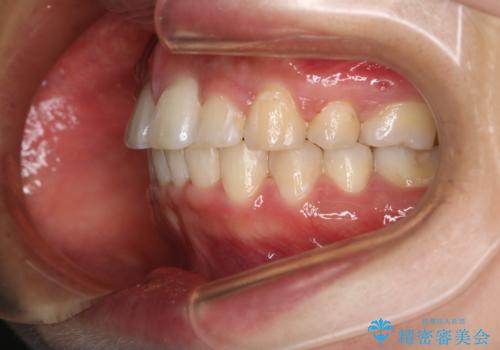

- 前歯のがたつきが気になるとご相談にいらした方です。当初は前歯の部分矯正をご希望されていましたが、全体的に整えることで審美的、機能的な歯並びとなりました。

当初は上顎前歯のみの部分矯正をご希望されていましたが、部分的に前歯のみを並べると出っ歯感がつよくなり、食事もしづらくなる可能性をお伝えしました。全顎的な矯正治療により、審美的、機能的な歯並びとなりました。